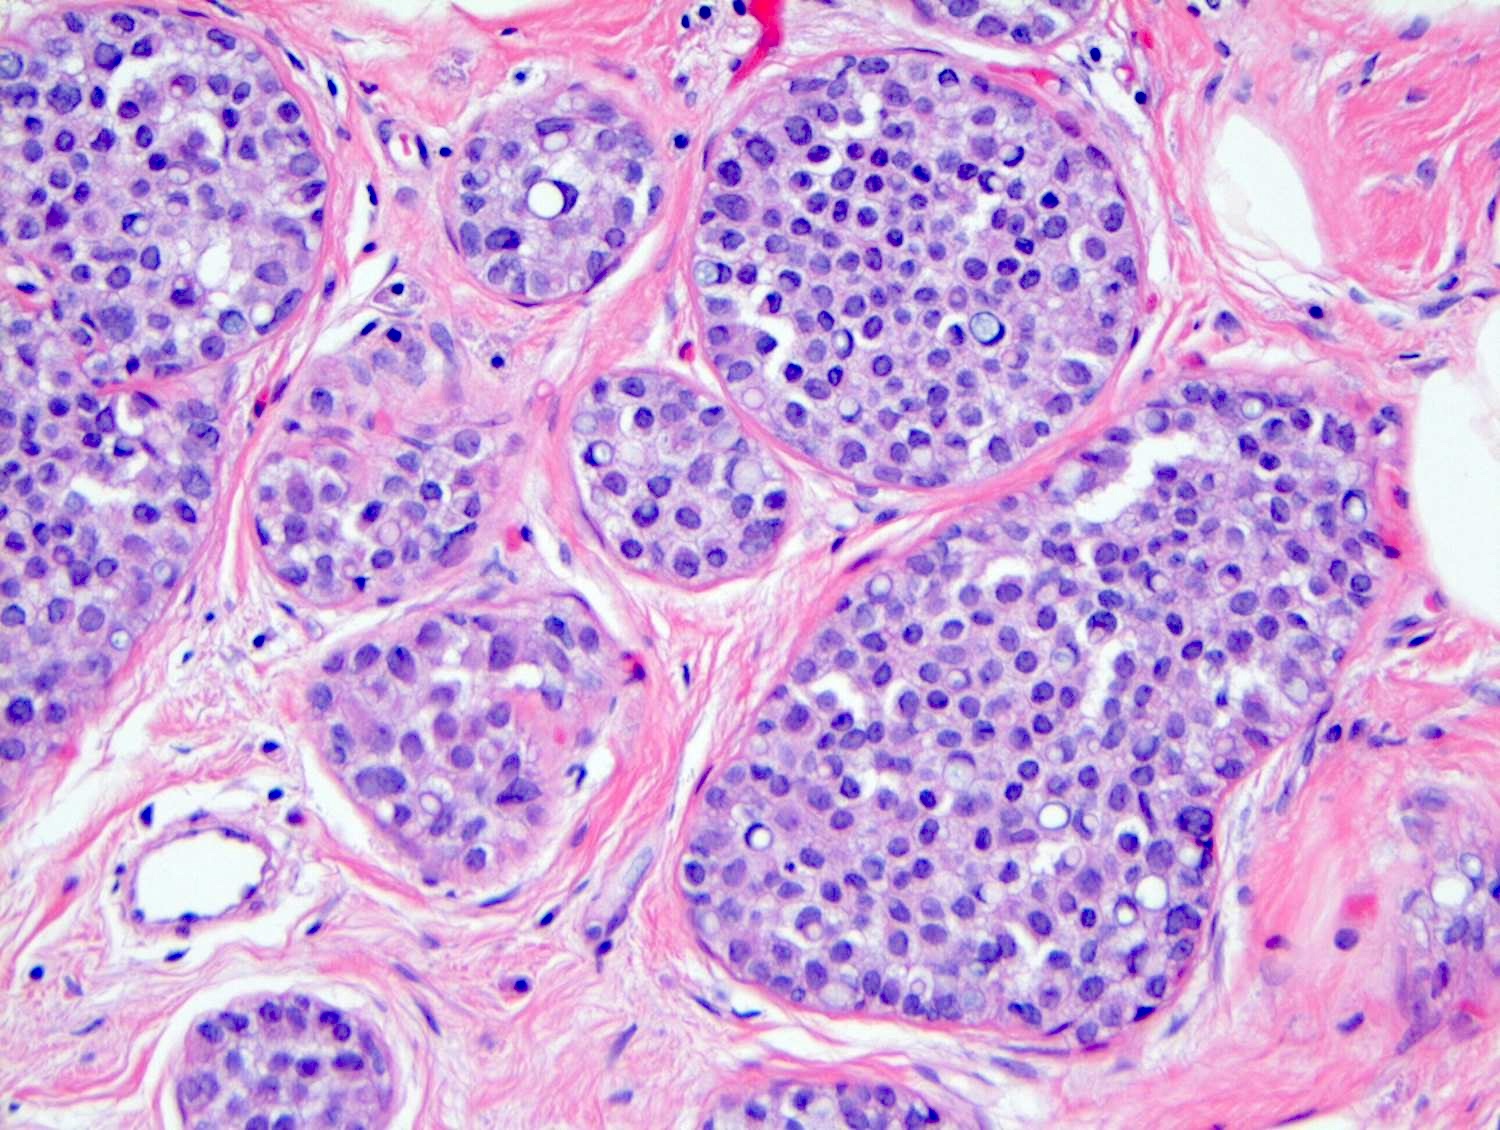

Microscopic (histologic) description

- LCIS involves the terminal duct lobular unit (TDLU), filling and distending acini

- > 50% of the acini in a TDLU must be filled and expanded to qualify as LCIS; otherwise, called atypical lobular neoplasia

- Lobular distention is defined as the presence of ≥ 8 cells in the cross sectional diameter of an acinus

- Involved lobules may be compared with uninvolved lobules to estimate the degree of distension

- Classic LCIS cells are monomorphic, evenly spaced, loosely cohesive and do not show polarization or gland formation

- 2 types of cells are described:

- Type A: nuclei are small to slightly enlarged (1 - 1.5x size of lymphocyte) with uniform round nuclei and inconspicuous nucleoli

- Type B: nuclei larger (2x size of lymphocyte), more abundant cytoplasm and more prominent nucleoli

- Type A and B cells can coexist in the same lesion

- Cytoplasm of LCIS cells is typically pale to lightly eosinophilic with indistinct cell borders

- In almost all cases of LCIS, at least some cells contain intracytoplasmic vacuoles or lumina, which may contain an eosinophilic globule; this feature is not specific to LCIS

- Vacuoles may be subtle such that special histochemical stains for mucin are required in order to demonstrate; alternatively, they may be large enough to push the nucleus against the cell membrane and produce signet ring cell forms

- Outer layer of myoepithelial cells is retained in the acini and ducts involved but it may be attenuated

- In some cases, scattered myoepithelial cells can be admixed with the neoplastic epithelial cells within the involved spaces

Microscopic (histologic) images

Contributed by Anna Biernacka, M.D., Ph.D.